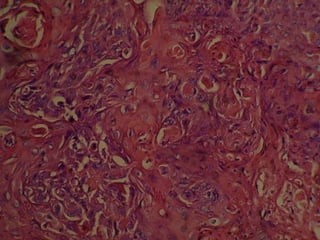

NEOPLASIA CARACTERISTICAS MICROSCOPICAS DE LAS CELULAS MALIGNAS. AUMENTO TAMAÑO NUCLEO (N/C) PLEOMORFISMO NUCLEAR. MITOSIS ATIPICAS CROMATINA GRUMOSA (MEMBRANA CELULAR  ENGROSADA) d)  PERDIDA DE LA ADHESIVIDAD.

NEOPLASIA CARACTERISTICAS MICROSCOPICASDE LAS CELULAS MALIGNAS. AUMENTO TAMAÑO NUCLEO (N/C) PLEOMORFISMO NUCLEAR. MITOSIS ATIPICAS CROMATINA GRUMOSA (MEMBRANA CELULAR ENGROSADA) d) PERDIDA DE LA ADHESIVIDAD.